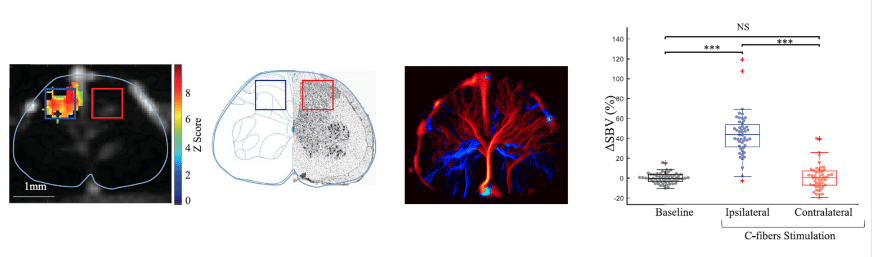

As well as being used to study the brain, fUS can also be used to study the response of the spinal cord to pain induced elsewhere in the body. This is very difficult with fMRI because of the movement due to breathing, but a combination of fUS neuroimaging and ultrasound localization microscopy (ULM) avoids this problem. Responses can therefore be mapped on an impressively small scale (see the figure), with obvious applications to spinal cord damage.